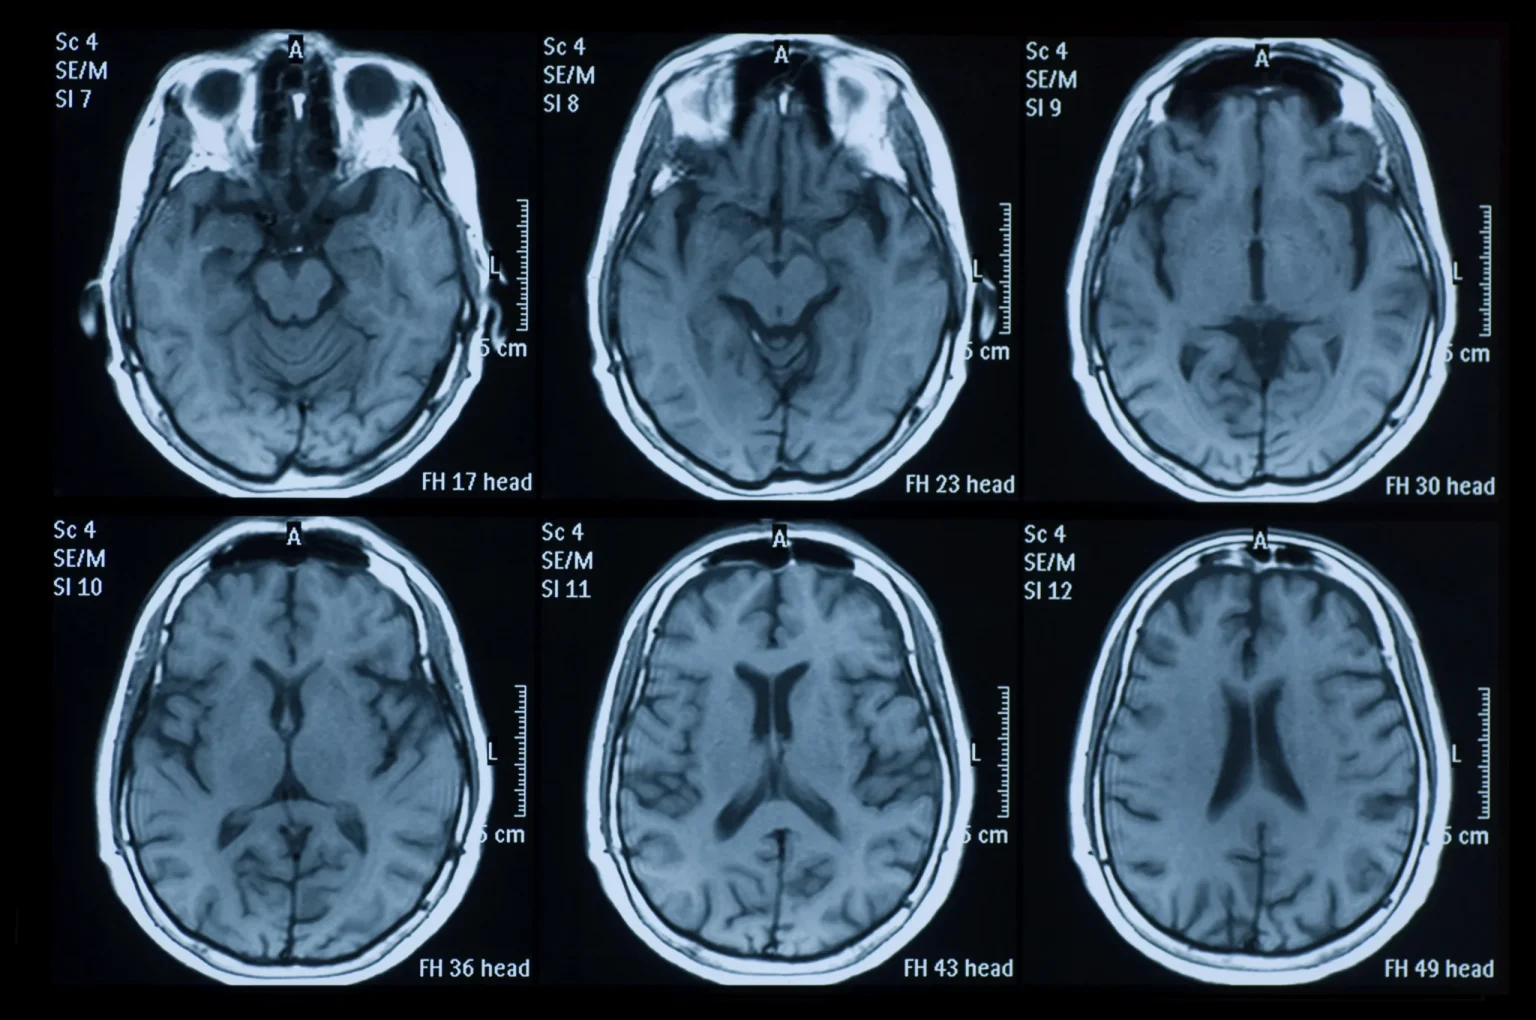

Το Πάρκινσον είναι μια προοδευτική και εξουθενωτική ασθένεια του εγκεφάλου που τελικά θέτει σε κίνδυνο την ικανότητα των ασθενών να περπατούν και ακόμη και να μιλάνε. Η διάγνωσή της είναι πολύπλοκη και στα αρχικά στάδια — αδύνατη. Η συνήθης μέθοδος οπτικοποίησης της δομής του εγκεφάλου χρησιμοποιεί μια τεχνική που ονομάζεται μαγνητική τομογραφία. Ωστόσο, δεν είναι αρκετά ευαίσθητη για να αποκαλύψει τις βιολογικές αλλαγές που λαμβάνουν χώρα στον εγκέφαλο ασθενών με Πάρκινσον και προς το παρόν χρησιμοποιείται, κυρίως, μόνο για τον αποκλεισμό άλλων πιθανών διαγνώσεων.